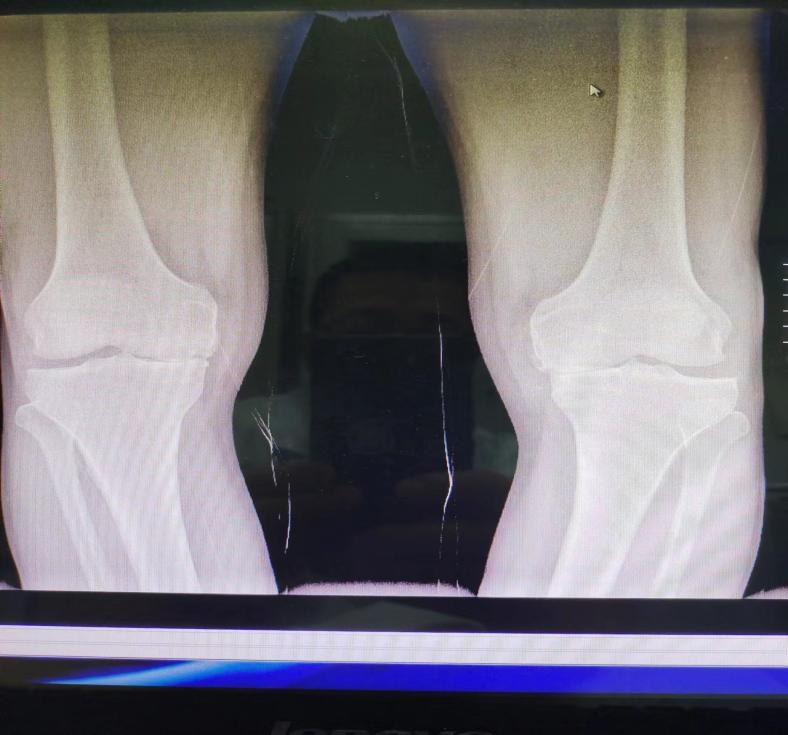

術(shù)前

患者趙先生,50歲,1年前開(kāi)始出現(xiàn)雙側(cè)膝關(guān)節(jié)疼痛,伴有嚴(yán)重內(nèi)翻畸形,嚴(yán)重影響正常生活。曾給予保守治療,療效差,于6月22日入院治療。完善相關(guān)檢查后,主任李海波對(duì)患者全面評(píng)估后,制定出最佳治療方案,計(jì)劃先行“左側(cè)膝關(guān)節(jié)單髁置換術(shù)”,待左膝關(guān)節(jié)傷口愈合、功能恢復(fù)后,再行“右側(cè)膝關(guān)節(jié)單髁置換術(shù)”。6月28日,在團(tuán)隊(duì)的共同努力下,手術(shù)成功完成。經(jīng)過(guò)為期2周的規(guī)范治療與功能鍛煉,患者恢復(fù)良好,改善了患者因膝關(guān)節(jié)骨性關(guān)節(jié)病帶來(lái)的困擾,生活質(zhì)量得到極大提高。